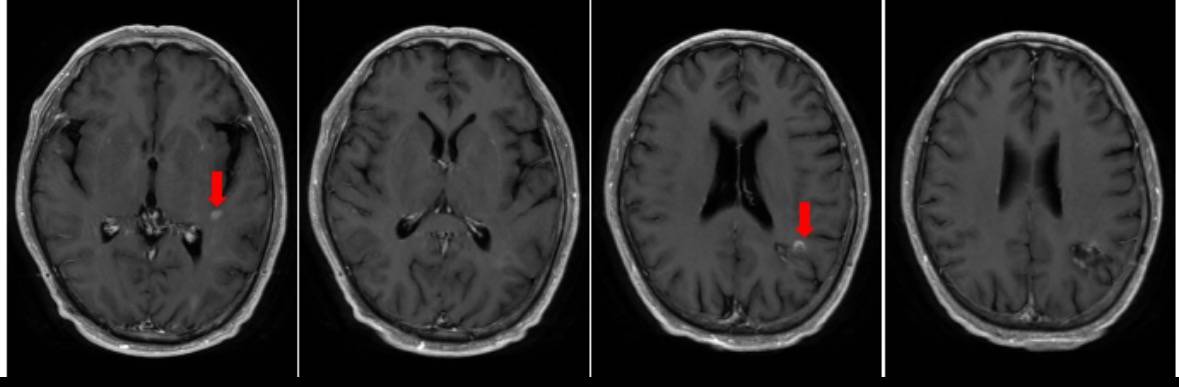

【典型病例】复发胶质母细胞瘤靶向联合免疫治疗效果显著

病史描述患者男性,54岁。2025年2月体检时发现左顶叶异常信号影,考虑胶质瘤可能性大。2025年3月8日行手术全切肿瘤,术后病理:(左顶)高级别胶质瘤,镜下呈胶质母细胞瘤形态,WHO 4级;建议行分子病理检测进一步明确诊断。免疫组化提示:MSH2、MSH6核表达缺失,提示微卫星不稳定。基因检测提示:MSI-H。术后行同步放化疗及替莫唑胺2周期化疗后,复查头颅核磁示颅内多发异常信号影,肿瘤复发可能